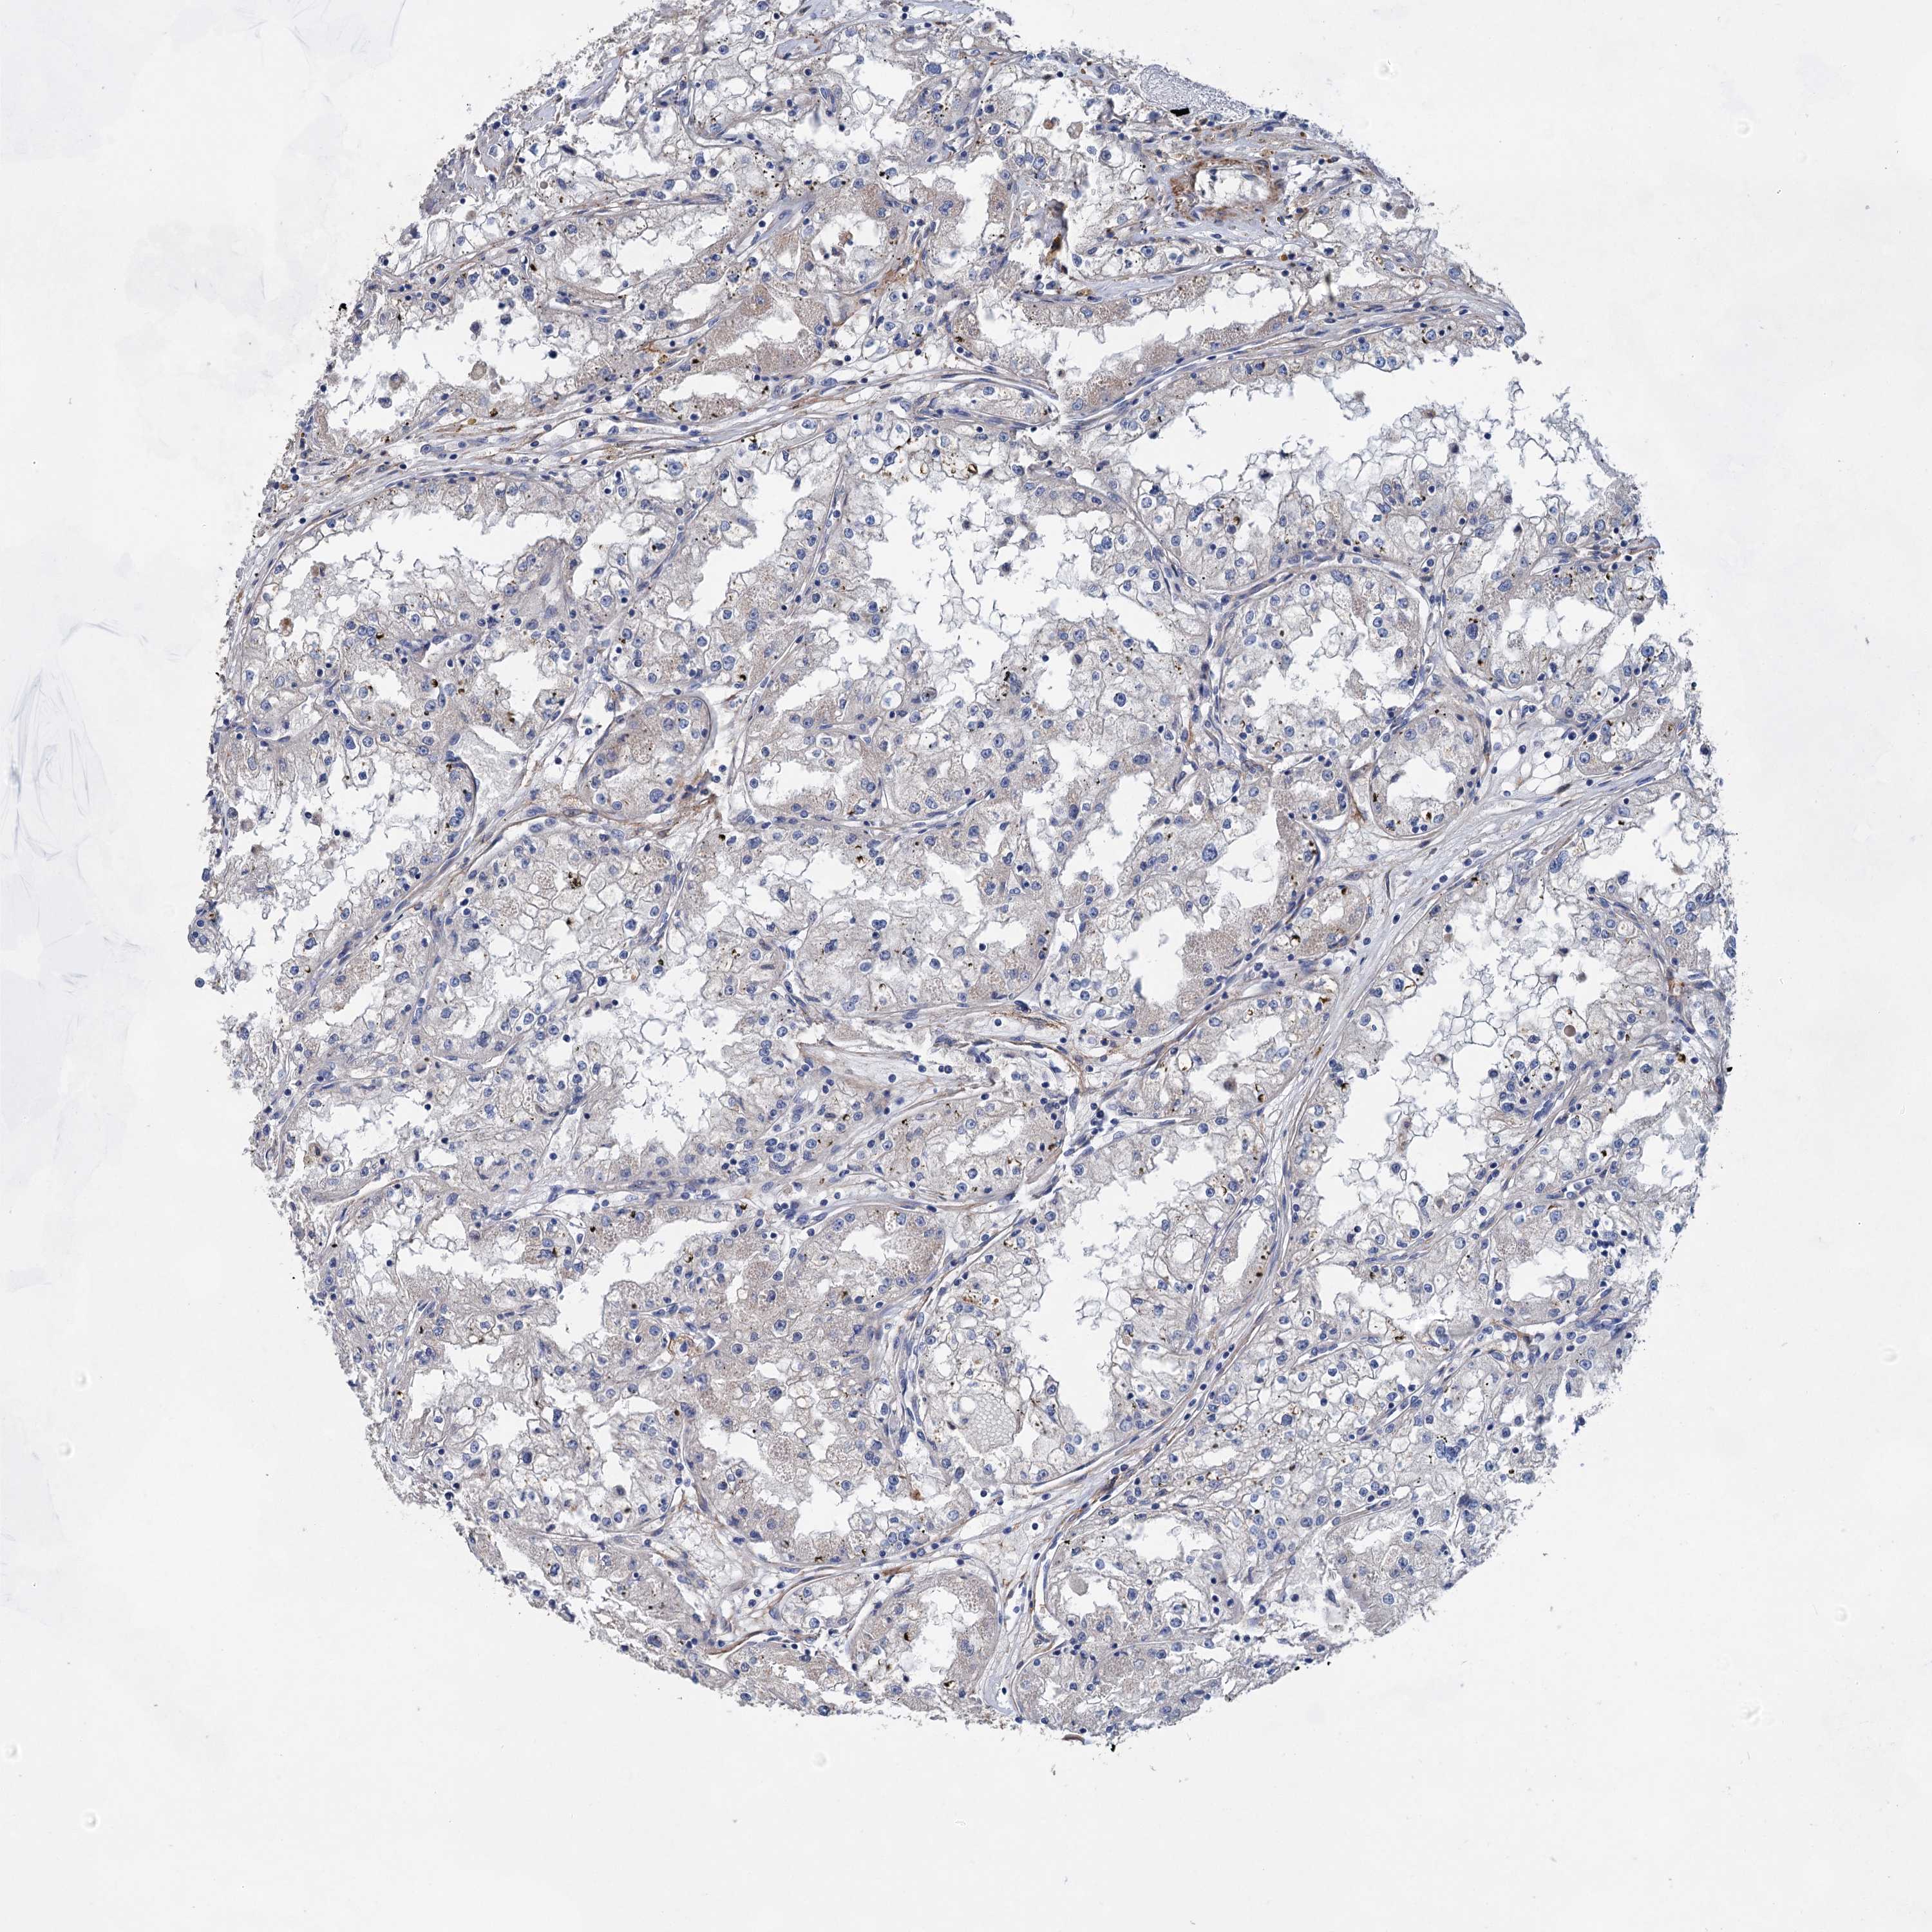

CANCER RENAL CANCER Show tissue menu

KICH TCGA KIRC TCGA KIRC VALIDATION KIRP TCGA PROTEIN RCC CPTAC PROTEIN EXPRESSION